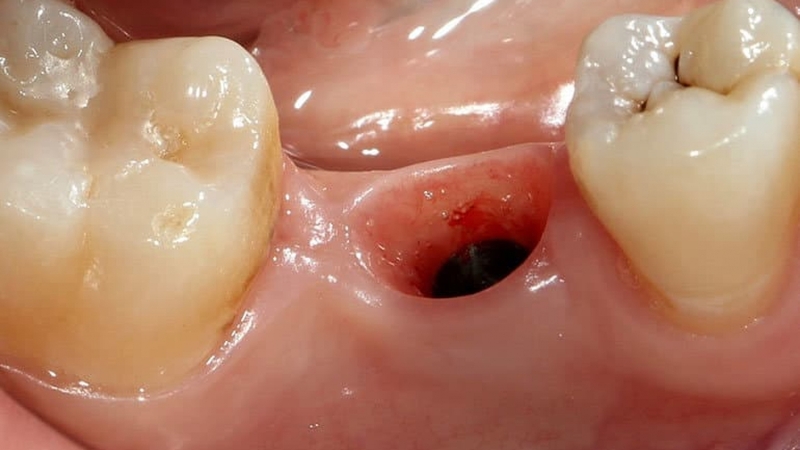

Sau một thời gian, lượng máu này sẽ dần dần đông lại và tạo nên cục máu đông sau khi nhổ răng. Nhiều người khi thấy có cục máu đông này không khỏi lo lắng, không biết có ảnh hưởng gì đến răng hay không. Đây là hiện tượng hết sức bình thường nên bạn không cần quá lo lắng nhé, cục máu đông này cho thấy vết thương đang lành lại nhanh chóng đấy.

Thông thường, cục máu đông sau khi nhổ răng sẽ xuất hiện sau khoảng 12 - 24 giờ, khi máu đã ngừng chảy. Bạn có thể nhận thấy xuất hiện một ít huyết tương kèm với cục máu đông này. Nhìn chung đây là biểu hiện cho thấy ổ răng đã được cầm máu thành công, cục máu đông cũng sẽ nhanh chóng biến mất sau đó, không gây ảnh hưởng nhiều đến sức khỏe răng miệng của bạn.

Sau khi nhổ răng sẽ để lại ổ răng trống, phần huyệt dưới ổ răng lộ ra ngoài dễ bị thức ăn lọt vào và gây nhiễm trùng không mong muốn. Chính vì vậy việc hình thành cục máu đông sau khi nhổ răng có ý nghĩa quan trọng trong việc bảo vệ phần ổ răng trống này, đặc biệt là huyệt răng. Cục máu đông làm giảm thiểu khả năng viêm xương ổ răng, khô ổ răng,...